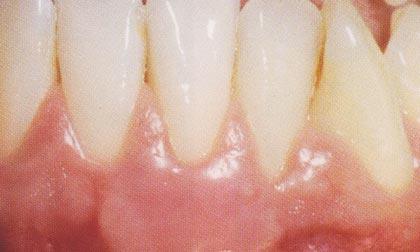

****************************หลังการรักษา

การตัดสินใจว่าจะใช้วิธีใดในการรักษา หรือแม้แต่ความสำเร็จในการรักษานั้น จะทำได้หรือไม่ขึ้นกับสาเหตุของโรค ความรุนแรงของภาวะเหงือกร่น และปัจจัยของเนื้อเยื่อ กระดูก และฟัน รวมถึงปัจจัยจากตัวผู้ป่วยเอง ซึ่งควรได้รับการวินิจฉัยจากทันตแพทย์ เพื่อประเมินภาวะดังกล่าว